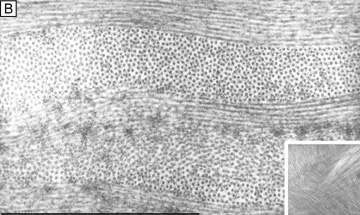

Fig. 10. (A) Low magnification (4,750×) TEM of predominantly orthogonally stacked lamellae in the middle third of cellular corneal stroma. (B) Higher magnification (72,500×) TEM of two lamellae in the middle third of cellular corneal stroma. One lamellae is in longitudinal view (top) and other is in cross-sectional view (bottom). Notice the uniformly 25-nm diameter collagen fibrils and the 40-nm diameter interfibrillar spaces that demonstrate only a short-range order (i.e., slight variability), but do not form a true crystalline lattice. (C) Cross-sectional diagram of collagen fibrils arranged in a true crystalline lattice arrangement. Size of a wavelength of light is shown above for comparison. Bars = 1 μm. (From Maurice DM. The structure and transparency of the cornea. J Physiol 136:263, 1957.)

Collagen type VI is the third most common type of collagen in the corneal stroma, but is unique in that it is only able to aggregate into repeating tetramers of type VI molecules. Thus, it forms only 10 to 15 nm diameter, beaded (20 × 30 nm diameter ovals with a periodicity of 100 nm), nonbanded filaments (Fig. 11A). Functionally, it acts as a bridging filament that binds corneal lamellae together where they cross each other (Fig. 11B, C). Along with fibril-associated collagens with interrupted triple helices (FACIT collagens, type XII and XIV collagen molecules), it also bridges intralamellar fibrils together (Fig. 11D).57,58 Overall, this three-dimensional, supramolecular scaffold created by human corneal stromal collagens results in a one-dimensional ordered (∼22 nm diameter collagen fibrils; ∼ 40 nm interfibrillar spaces × random directionality) 12-μm thick acellular Bowman's layer (Figs. 12A and 13A) and a three-dimensionally-ordered (∼25 nm diameter collagen fibrils; ∼ 40 interfibrillar spaces × parallel directionality) series of successive stacks of lamellae in the cellular stroma measuring in the center of cornea around 450 μm in thickness.59–61

Although difficult to count exactly, the central cornea has been found to have approximately 300 corneal lamellae, whereas the peripheral cornea has approximately 500.61 Although these lamellae are generally described as running parallel to the corneal surface in orthogonal directions to one another, regional difference exist in their size, directionality, and amount of interweaving. The anterior third of the cellular corneal stroma has thinner (0.2- to 1.2-μm thick), narrower (0.5- to 30-μm wide), and mostly obliquely oriented lamellae with extensive vertical and horizontal interweaving (Figs. 12B and 13B), whereas the posterior two-thirds has thicker (1- to 2.5-μm thick), wider (100- to 200-μm wide), and mostly parallel oriented lamellae with only slight horizontal interweaving (Figs. 12C and 13C).60